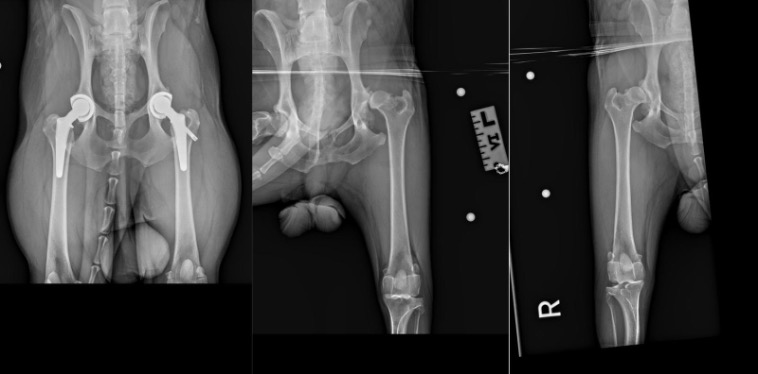

“I was so worried,” remembered his owner, Ms Lina Hoo. “He is usually so active, and he was so young, too.” After observing Asahi’s increasing pain, Lina took him to his regular vet at Ohana VetCare, where an X-ray revealed advanced arthritis in both hips with partial luxation on the left. He was referred to Beecroft Hospital on the same day.

Asahi’s first surgery was performed smoothly with successful integration of the prosthetic hip. However, strict post-operative confinement was essential.

New signs of trouble emerged after a swim session in 2024. His right hip had worsened, and Lina did not hesitate to pencil in a second surgery. Due to the stability now present on the left leg, the recovery from the right hip replacement was notably faster, taking only about two months.

Today, Asahi has returned to his energetic self, free from the pain that once limited his movements. His successful bilateral replacement demonstrates how this approach can transform a young dog’s prognosis from one of chronic disability to that of everyday mobility.